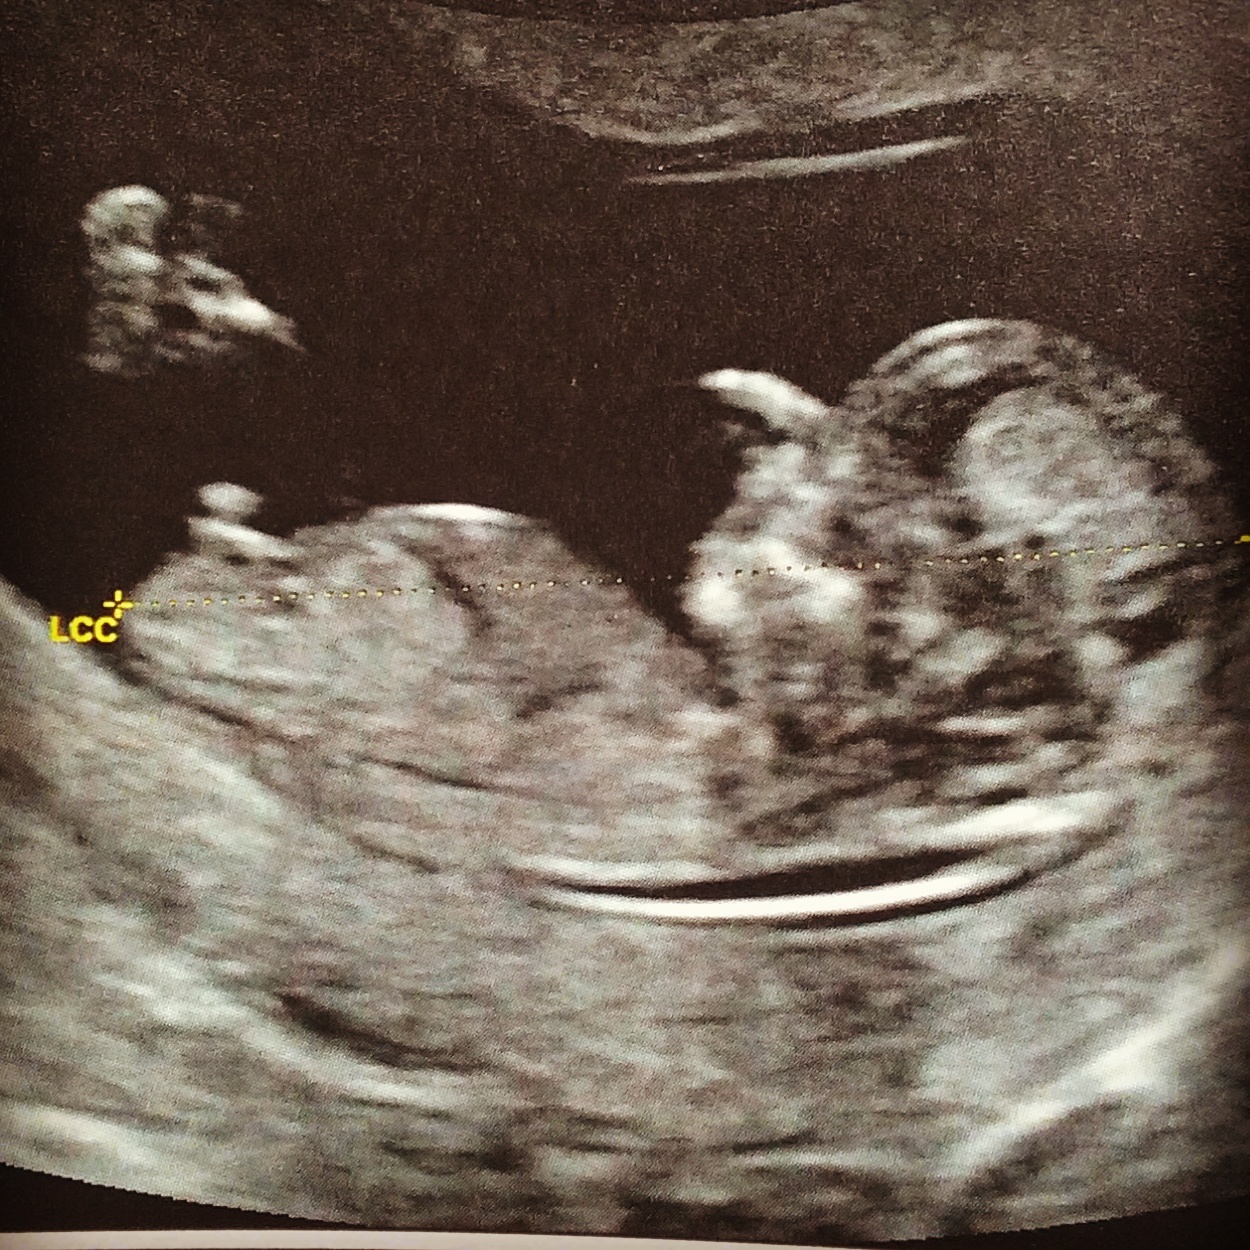

Voilà le chaton ! Position « cool » avec chevilles croisé et bras derrière la tête… il ronflait !

Première écho forte en émotion ! On attendait depuis 3 mois… et c’est toujours aussi magique!

Le petit coeur va bien tout est en place … à comparé avec maiwenn pour le même « âge » ici on a 2cm de plus! Ca promet 🙂

Bilan: bonne tension pour moi. Pas pris un kilo. Toujours un peu de fatigue mais plus de nausées.

Pour bébé tout roule! On a fait les tests pour écarté les risques de trisomie .mais il est bien au chaud !

Maiwenn le surveille.

Pour le sexe on a pas besoin de demander maiwenn et moi savons déjà depuis le début que c’est un garçon! Alors on verra.